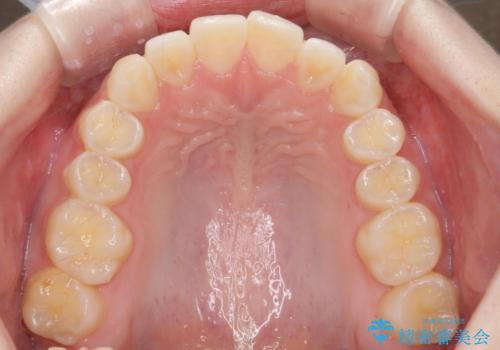

前歯のねじれを治したい マウスピース矯正治療

- 前歯のねじれを改善し、きれいな歯並びにしたい!と矯正治療を希望され来院されました。

マウスピース矯正システム、インビザラインのシミュレーションを用いて最終的な歯の位置をしっかりと確認したのち、きれいな歯並びとなるようマウスピース矯正治療を開始します。

ねじれとともに突き出たように見えていた前歯も見た目が大きく改善し、喜んでいただくことができました。